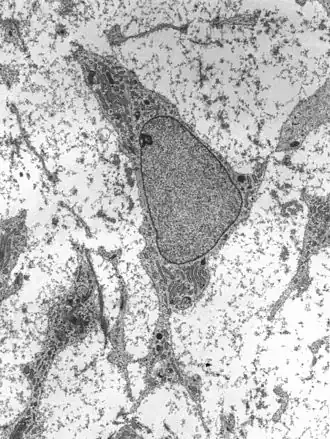

![]() Transmission electron micrograph of a mesenchymal stem cell displaying typical ultrastructural characteristics | |

Adult stem cells are found in a few select locations in the body, known as niches, such as those in the bone marrow or gonads. They exist to replenish rapidly lost cell types and are multipotent or unipotent, meaning they only differentiate into a few cell types or one type of cell. In mammals, they include, among others, hematopoietic stem cells, which replenish blood and immune cells, basal cells, which maintain the skin epithelium, and mesenchymal stem cells, which maintain bone, cartilage, muscle and fat cells. Adult stem cells are a small minority of cells; they are vastly outnumbered by the progenitor cells and terminally differentiated cells that they differentiate into.[1]

Mesenchymal stem cells

Mesenchymal stem cells (MSC) or mesenchymal stromal cells, also known as medicinal signaling cells are known to be multipotent, which can be found in adult tissues, for example, in the muscle, liver, bone marrow and adipose tissue. Mesenchymal stem cells usually function as structural support in various organs as mentioned above, and control the movement of substances. MSC can differentiate into numerous cell categories as an illustration of adipocytes, osteocytes, and chondrocytes, derived by the mesodermal layer.[34] Where the mesoderm layer provides an increase to the body's skeletal elements, such as relating to the cartilage or bone. The term "meso" means middle, infusion originated from the Greek, signifying that mesenchymal cells are able to range and travel in early embryonic growth among the ectodermal and endodermal layers. This mechanism helps with space-filling thus, key for repairing wounds in adult organisms that have to do with mesenchymal cells in the dermis (skin), bone, or muscle.[35]

Mesenchymal stem cells are known to be essential for regenerative medicine. They are broadly studied in clinical trials. Since they are easily isolated and obtain high yield, high plasticity, which makes able to facilitate inflammation and encourage cell growth, cell differentiation, and restoring tissue derived from immunomodulation and immunosuppression. MSC comes from the bone marrow, which requires an aggressive procedure when it comes to isolating the quantity and quality of the isolated cell, and it varies by how old the donor. When comparing the rates of MSC in the bone marrow aspirates and bone marrow stroma, the aspirates tend to have lower rates of MSC than the stroma. MSC are known to be heterogeneous, and they express a high level of pluripotent markers when compared to other types of stem cells, such as embryonic stem cells.[34] MSCs injection leads to wound healing primarily through stimulation of angiogenesis.[36]